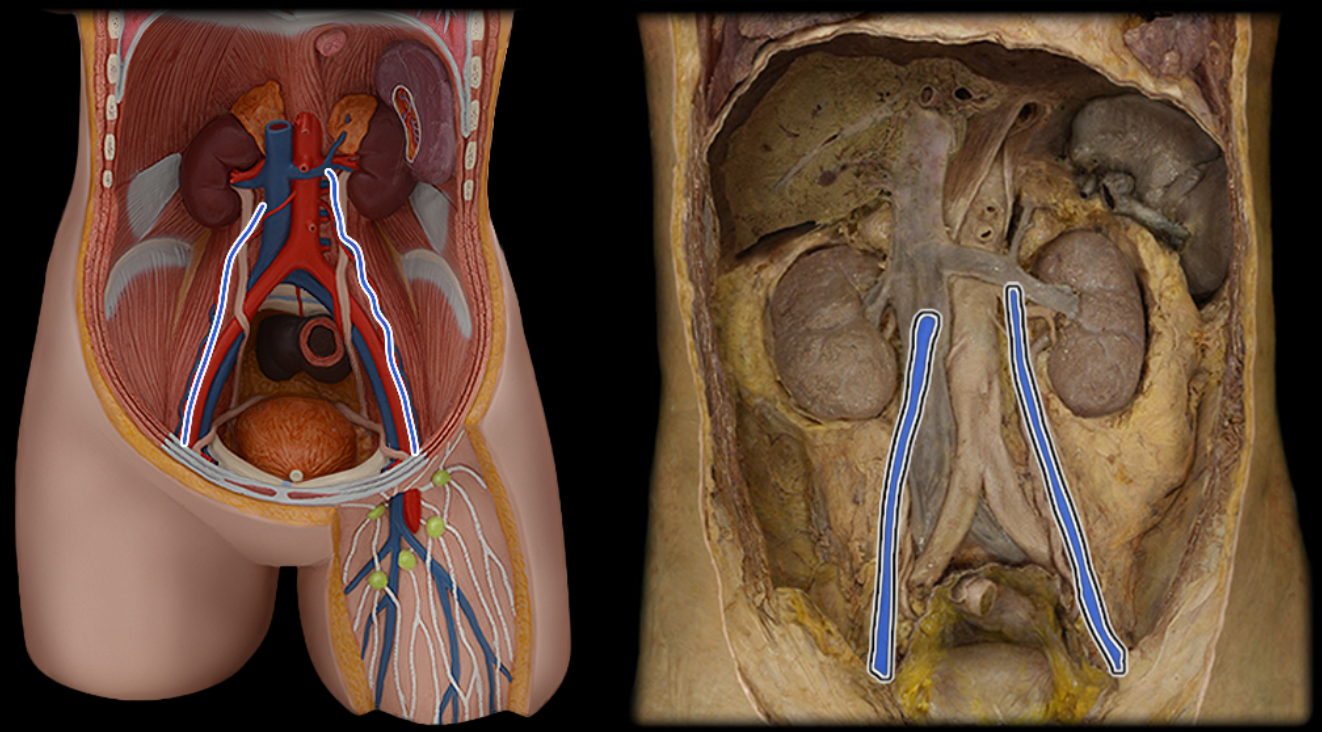

Abdominal aorta

Common iliac a.

Common iliac v.

External iliac a.

External iliac v.

Femoral a.

Femoral v.

Gonadal a.

Gonadal v.

Inferior vena cava

Lumbar a.

Lumbar v.

Renal a.

Renal v.

Superior mesenteric a.